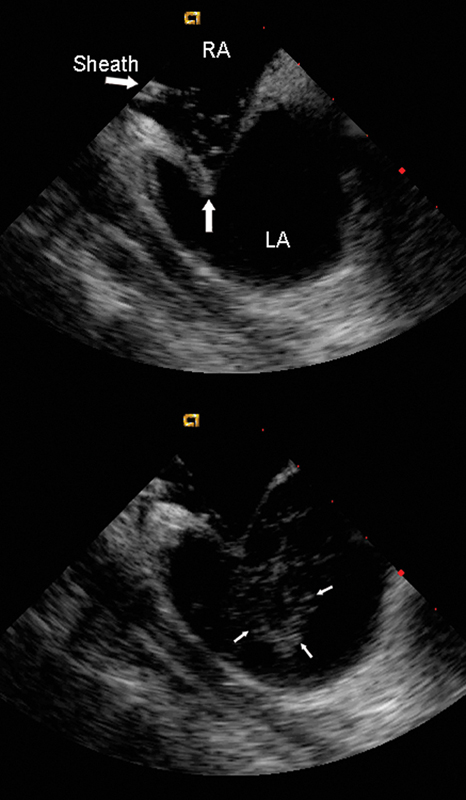

فحوصات تشخيصية لبعض امراض القلب والشرايين التاجية